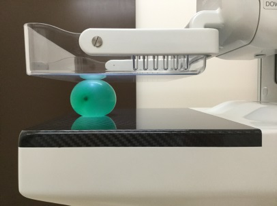

装置の紹介

当院では2016年5月に乳房撮影装置

MAMMOREX Pe・ru・ru DIGITAL

(キヤノンメディカルシステムズ)を導入しました。

FPDを搭載した装置で、解像力やコントラストが向上し微細な石灰化や腫瘤をより鮮明に描出することが可能です。検査は健診棟の女性専用エリア内に併設されたマンモグラフィ専用の検査室で行っており、安心して検査を受けていただけます。撮影はNPO法人日本乳がん検診精度管理中央機構の認定を受けた女性技師が担当します。

圧迫の必要性

厚みのある乳房の中にはたくさんの乳腺や脂肪などが重なって存在しています。

これらを均等に伸ばし組織同士の重なりを分離することで、小さなしこりや石灰化の粒をより見つけやすい画像にすることができます。

*実際に乳房を圧迫する時間は1枚の撮影で数十秒程度です。

画像1枚目:圧迫なし、画像2枚目:圧迫あり

水風船の中に花型のビーズをいれました。

厚みを約半分にしたことで、形がはっきり見えるようになります。